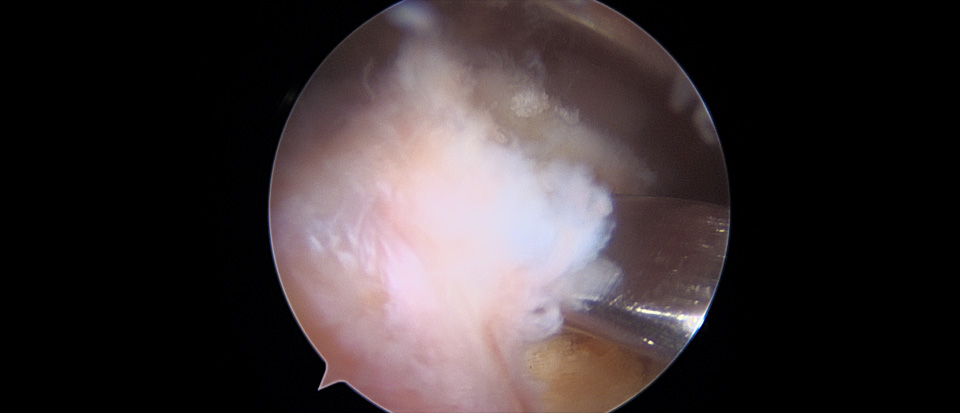

수술중 관절경 사진으로 견봉하 충돌되는 골조직을 갈아낸다.

- 환자 동의하에 게시된 이미지입니다.

수술중 관절경 사진으로 견봉하 충돌되는 골조직이 제거된 것을 확인할 수 있다.